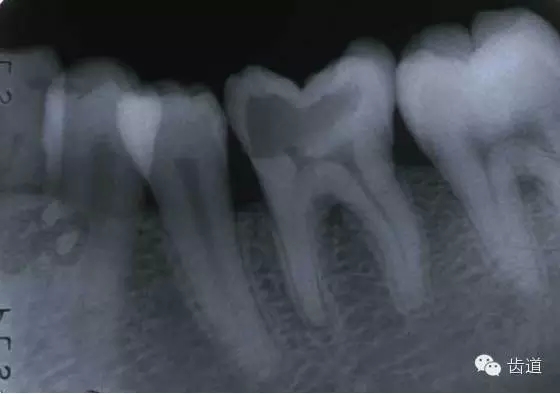

牙折分為冠折、根折及冠根折三種。根管治療后,由于牙折導(dǎo)致拔除者屢見(jiàn),故應(yīng)引起足夠重視。

3.根管清理和成形以及做冠樁預(yù)備過(guò)程中,過(guò)多的磨除根管壁,削弱了牙根強(qiáng)度。

4.用牙膠做根管充填時(shí),側(cè)向或垂直壓力過(guò)大,均可造成牙根縱折。

5.其他:根管釘、樁的采用;熱塑冷凝的牙膠尖填入根管后自身體積膨脹;牙周受累的牙齒,支持骨喪失,也增加了牙折的機(jī)會(huì)。